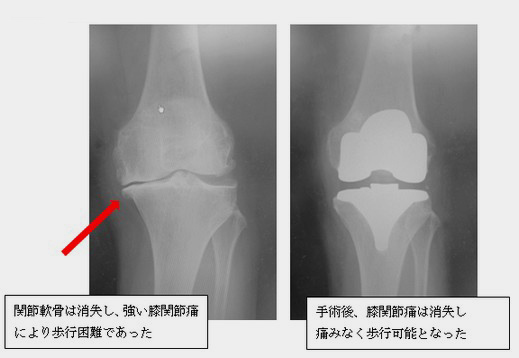

人工膝関節置換術

人工膝関節置換術の適応は、関節軟骨が破壊され、下肢の変形が進んだために、疼痛が強く日常生活をおくるにあたってかなり支障をきたす方です。(膝関節の痛みの原因も多種にわたるため、疼痛が強いからといって必ずしもこの手術が必要なわけではありません。) 人工関節の材料として一般的にはコバルト合金、チタン合金などが使われています。長所としては、①高い除痛効果がある、②術後早期から荷重ができる、③入院期間が短い(当科では術後3-4週間で退院)、④高度な変形にも対応できるが挙げられますが、短所としては、①関節可動域が犠牲になることがある、②人工物であるため再手術が必要になることがあることがあります。

手術方法を簡単に解説すると、傷んだ関節軟骨を切除してそこに金属などの人工物をかぶせ、下肢の変形を矯正することです。関節置換といっても膝関節そのものをいれかえるわけではありません。虫歯の治療でいえば、入れ歯にするのではなく、金歯/銀歯をかぶせると考えると良いと思います。